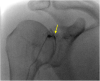

The rotator cuff is a group of four muscles and tendons surrounding the shoulder joint providing it strength and stability. The rotator cuff consists of the subscapularis, supraspinatus, infraspinatus and teres minor. Many shoulder complaints are caused by rotator cuff pathology such as impingement syndrome, tendon tears and other diseases e.g. calcific tendonitis. Diagnosis starts with clinical history and physical examination, after which imaging is often used to help confirm clinical findings depending on the differential diagnosis. The aim of the article is to review the frequently used imaging modalities to assess the rotator cuff and cuff-related disease, specifically focusing on radiography, ultrasonography and magnetic resonance imaging. This article will outline the advantages and disadvantages for each modality and illustrate typical radiological findings of common rotator cuff pathologies.